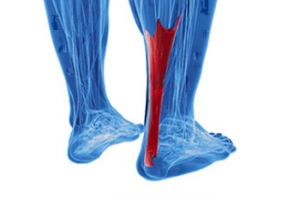

Facts About Achilles Tendon Pain

Achilles tendonitis is a condition that affects the large tendon at the back of the ankle that connects the calf muscles to the heel bone. It develops when the tendon becomes irritated from repeated strain or overuse during activities like walking, running, or jumping. Symptoms include pain, stiffness, swelling, and difficulty pushing off the foot, especially after rest. There are two types, based on where the tendon is affected, either in the middle or near the heel. Risk factors include tight calf muscles, sudden increases in activity, aging, and wearing poor-fitting shoes. A podiatrist can evaluate the tendon, check foot structure, and order imaging to confirm the diagnosis. Treatment may include bracing, orthotics, or surgery if the tendon is damaged. If you have symptoms of Achilles tendonitis, it is suggested that you make an appointment with a podiatrist for a diagnosis and treatment.

Achilles tendon injuries need immediate attention to avoid future complications. If you have any concerns, contact Brian D. Jackson, DPM of Neuhaus Foot and Ankle. Our doctor can provide the care you need to keep you pain-free and on your feet.

What Is the Achilles Tendon?

The Achilles tendon is a tendon that connects the lower leg muscles and calf to the heel of the foot. It is the strongest tendon in the human body and is essential for making movement possible. Because this tendon is such an integral part of the body, any injuries to it can create immense difficulties and should immediately be presented to a doctor.

There are various types of injuries that can affect the Achilles tendon. The two most common injuries are Achilles tendinitis and ruptures of the tendon.

Achilles Tendinitis Symptoms

- Inflammation

- Dull to severe pain

- Increased blood flow to the tendon

- Thickening of the tendon

Rupture Symptoms

- Extreme pain and swelling in the foot

- Total immobility

Treatment and Prevention

Achilles tendon injuries are diagnosed by a thorough physical evaluation, which can include an MRI. Treatment involves rest, physical therapy, and in some cases, surgery. However, various preventative measures can be taken to avoid these injuries, such as:

- Thorough stretching of the tendon before and after exercise

- Strengthening exercises like calf raises, squats, leg curls, leg extensions, leg raises, lunges, and leg presses

What are Achilles Tendon Injuries

The Achilles tendon is the strongest tendon in the human body. Its purpose is to connect the lower leg muscles and calf to the heel of the foot. This tendon is responsible for facilitating all types of movement, like walking and running. This tendon provides an enormous amount of mobility for the body. Any injuries inflicted to this tissue should be immediately brought up with a physician to prevent further damage.

The most common injuries that can trouble the Achilles tendon are tendon ruptures and Achilles tendinitis. Achilles tendinitis is the milder of the two injuries. It can be recognized by the following symptoms: inflammation, dull-to-severe pain, increased blood flow to the tendon, thickening of the tendon, and slower movement time. Tendinitis can be treated via several methods and is often diagnosed by an MRI.

An Achilles tendon rupture is trickier to heal, and is by far the most painful injury. It is caused by the tendon ripping or completely snapping. The results are immediate and absolutely devastating, and will render the patient immobile. If a rupture or tear occurs, operative and non-operative methods are available. Once the treatment begins, depending on the severity of the injury, recovery time for these types of issues can take up to a year.

Simple preventative measures can be taken as a means to avoid both injuries. Prior to any movement, taking a few minutes to stretch out the tendon is a great way to stimulate the tissue. Calf raises, squats, leg curls, leg extensions, leg raises, lunges, and leg presses are all suggested ways to help strengthen the lower legs and promote Achilles tendon health.

Many problems arise among athletes and people who overexert themselves while exercising. Problems can also happen among those who do not warm up properly before beginning an activity. Proper, comfortable shoes that fit correctly can also decrease tendon injuries. Some professionals also suggest that when exercising, you should make sure that the floor you are on is cushioned or has a mat. This will relieve pressure on the heels. A healthy diet will also increase tendon health.

It is very important to seek out a podiatrist if you believe you have an injury in the Achilles region. Further damage could result in severe complications that would make being mobile difficult, if not impossible.